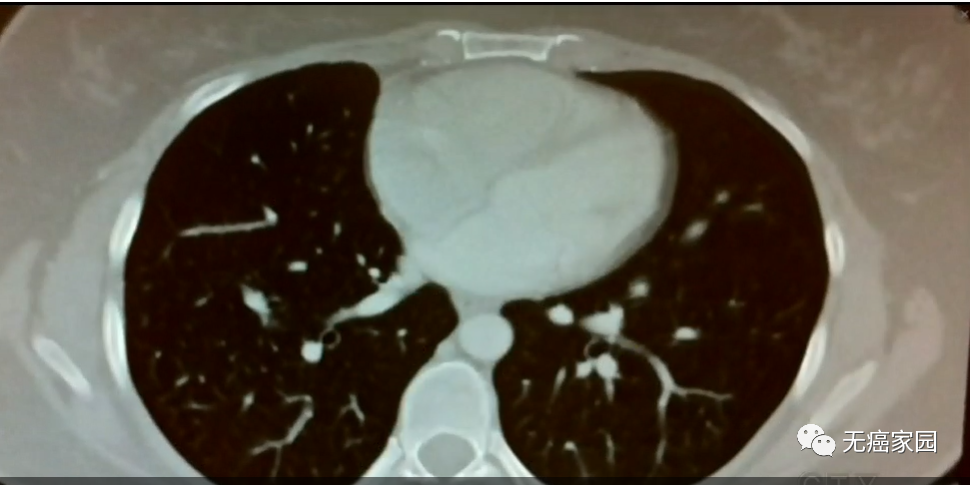

这是一位肺癌晚期广泛转移患者,2003年就被判“死刑”,但靠着正规治疗,尤其是靶向药物帮助下,存活了15年,而且越来越健康!相信科学,积极心态,再加上运气,她打破了传统结论,成了给无数人带来正能量的奇迹。

据无癌家园的专家介绍道:根据患者的基因突变,医生决定用特定药物的靶向治疗在肺癌中已经成为一种有效的治疗手段。截止到目前为止,已经有阳性意义基因突变的肺癌患者,已经达到非小细胞肺癌患者总数的70%,这意味着将有70%的非小细胞肺癌患者可以通过基因检测找到对应的靶向药物,从而延长生存周期,提高生存质量。